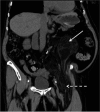

Patients with retroperitoneal sarcoma can present to a variety of clinicians with non-specific symptoms and retroperitoneal sarcomas can be incidental findings. Failure to recognize retroperitoneal sarcomas on imaging can lead to inappropriate management in non-specialist centers. Therefore it is critical that the possibility of retroperitoneal sarcoma should be considered with prompt referral to a soft tissue sarcoma unit. This review guides clinicians through a diagnostic pathway, introduces concepts in response assessment and new imaging developments.